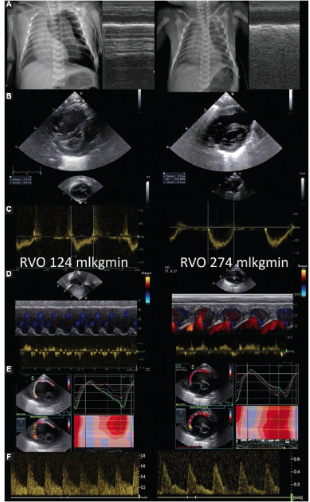

IntroductionThe asynchronous-abdominal curtain sign (A-ACS) is a suggestive ultrasound artifact for pneumothorax in veterinary medicine. However, its specifi...